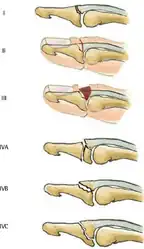

- Doyle classification of mallet fingers[7]